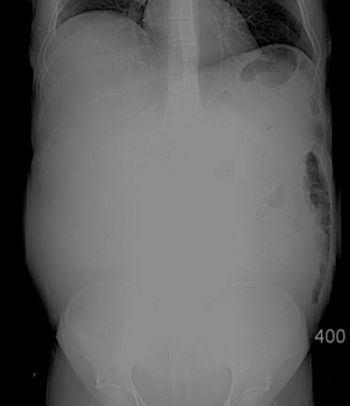

A 2-day-old baby fails to pass meconium - what is your diagnosis?